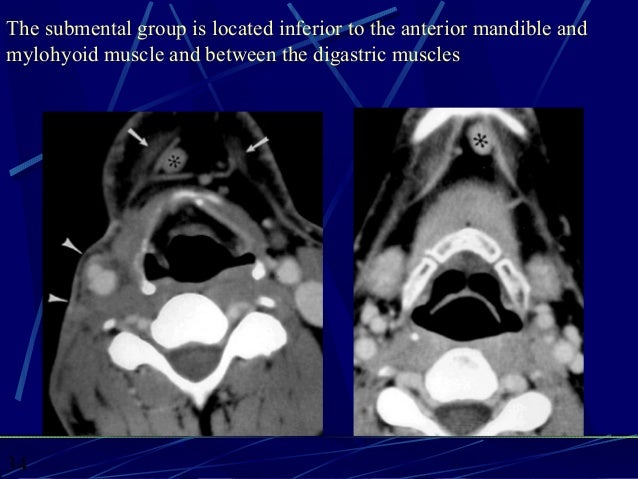

CT ANATOMY OF THE NECK SPACES

submental